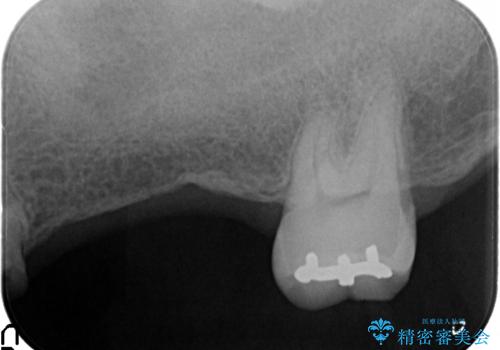

・重度虫歯による残根状態・欠損歯→インプラント補綴

・対合歯の欠損による歯の挺出→マイクロインプラントを用いた小矯正を行うことで咬合平面を是正

今回、左下6は頬側歯頚部に虫歯があり圧下を行ったことからクラウンにより補綴を行いました。